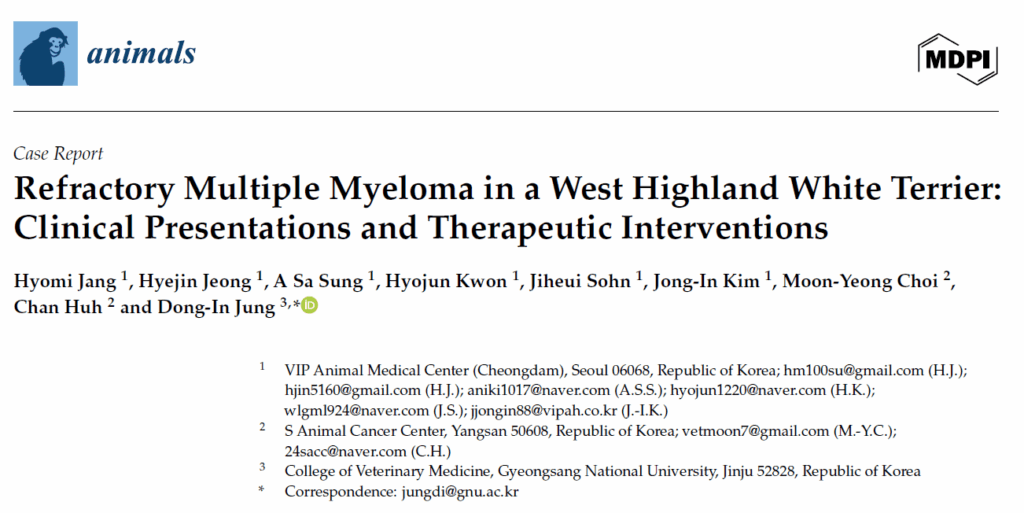

因双侧后肢共济失调就诊于当地动物医院。最初症状类似于跛行,怀疑是关节疾病。给予非甾体抗炎药治疗3周,但症状逐渐加重。随后进行了CT和MRI。影像学检查发现第三腰椎椎体处有一肿块,压迫L3-L4水平脊髓。在多个椎体(包括髂骨、耻骨和肋骨)中也检测到肿块。还观察到纵隔和腹部淋巴结肿大,肝脏肿大且存在低密度肝病变,肝脏、脾脏、右肾上腺和肾脏实质变化,这些表现引发了对多发性骨髓瘤的怀疑(下图)。随后该犬被转诊接受化疗。

↑ CT结果。在横断面(未增强)图像上,L3水平肿块(箭头)和椎体骨溶解(A)。在胸椎和腰椎的多个区域观察到低密度区域(未增强)(箭头)(B)。在髂骨(箭头)(C)和耻骨(箭头)(D)区域发现骨溶解病变(增强后)。纵隔淋巴结(箭头)(E)和肝脏(箭头)(F)显著肿大(增强后)。